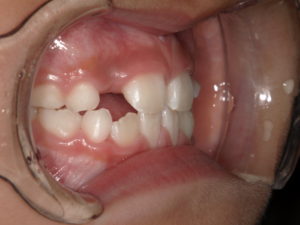

| 治療期間・回数 | 動的治療期間3カ月。5回。 |

| 治療方法 | リンガルアーチによる前歯の被害改善。 |

リンガルアーチで1カ月半で動きました。

治療後